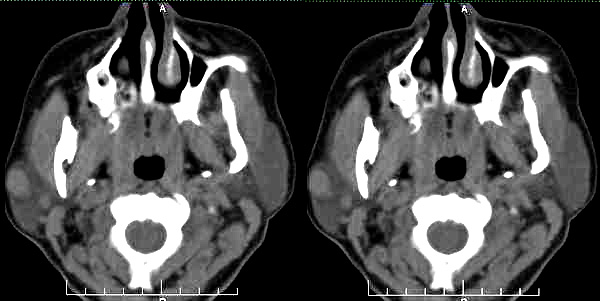

标题: CT2109:右腮腺区肿物

女35岁,右腮腺区肿物一年余

肿块边界清楚锐利,考虑腮腺混合瘤,建议增强。

病史长,病灶光滑锐利、密度均匀,未见坏死,右侧腮腺浅叶的混合瘤首先考虑

右侧腮腺浅叶圆形稍高密度影,边缘光整,考虑腮腺囊腺淋巴瘤。